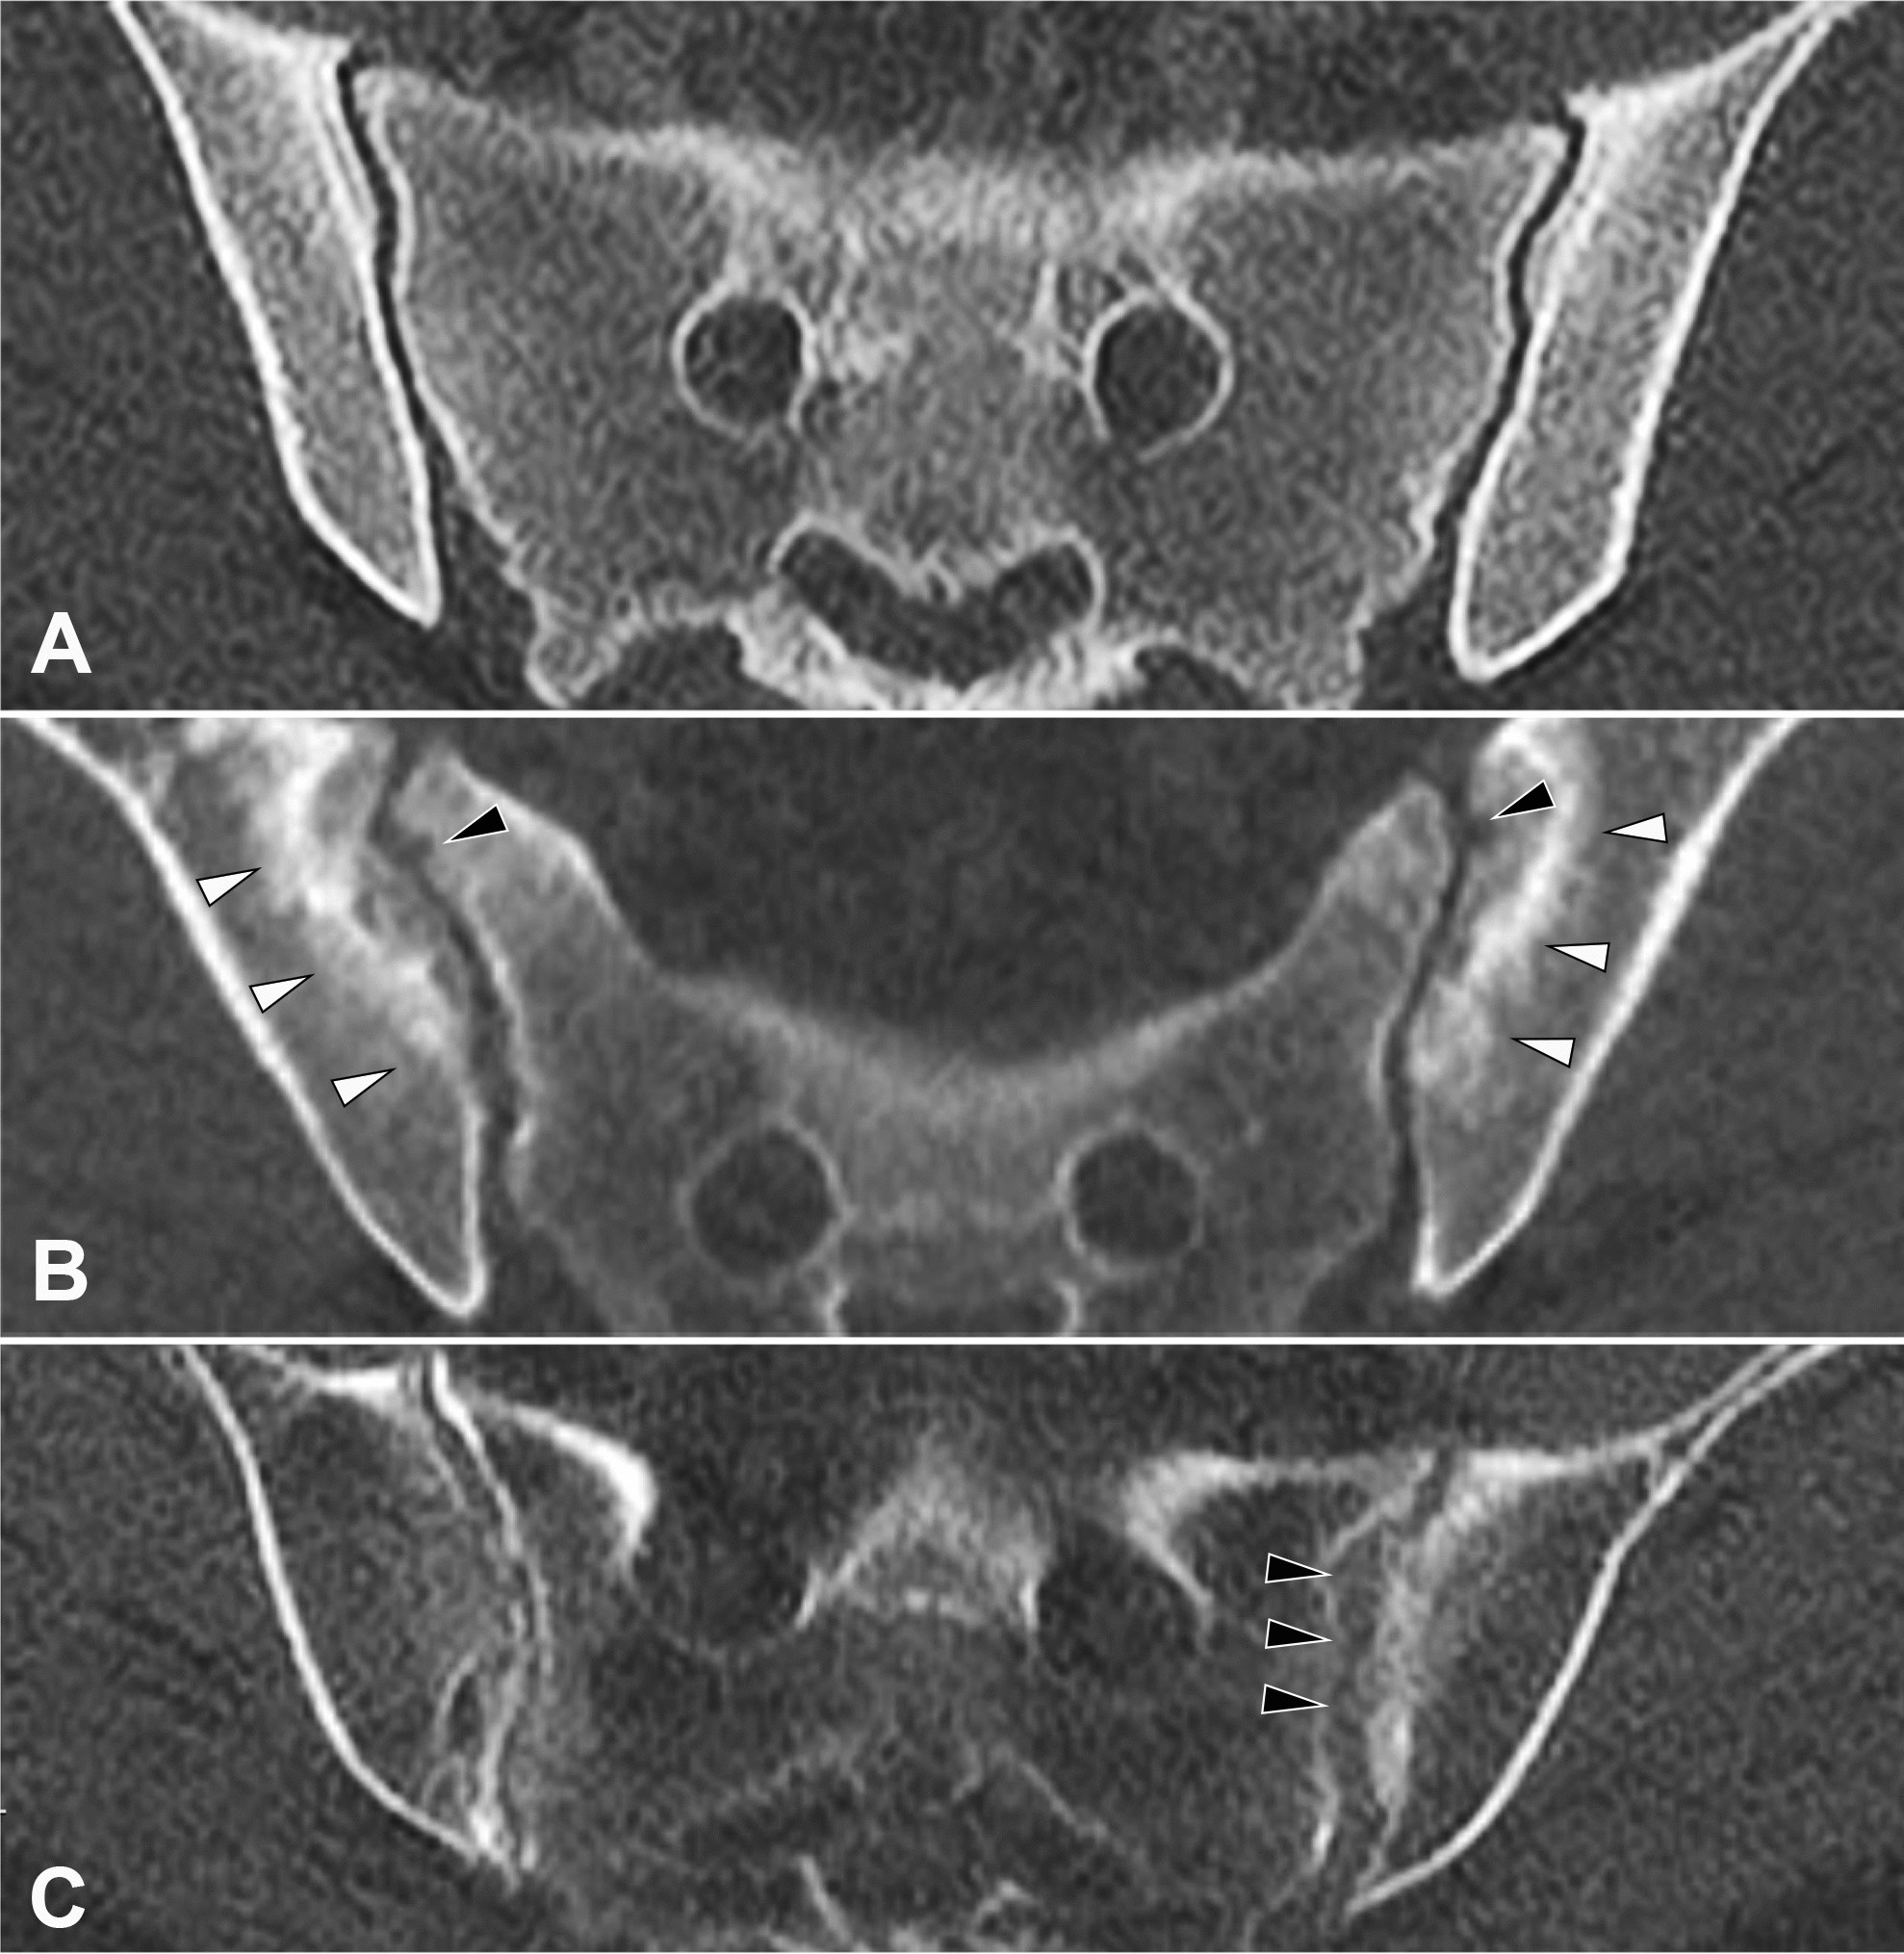

Figure 2

From: Asymptomatic secondary hyperparathyroidism can mimic sacroiliitis on computed tomography

Example of joint alterations in sHPT. Axially reconstructed high-resolution CT images. (A) Healthy control patient with normal SIJ. (B) Patient with secondary hyperparathyroidism: note the subchondral bone resorption mimicking erosions (black arrowheads) as well as the sclerotic rim around the resorption zone (white arrowheads). (B) Patient with secondary hyperparathyroidism: note the irregular, pseudo-widened left joint space (black arrowheads) compared to the regular joint space on the right.